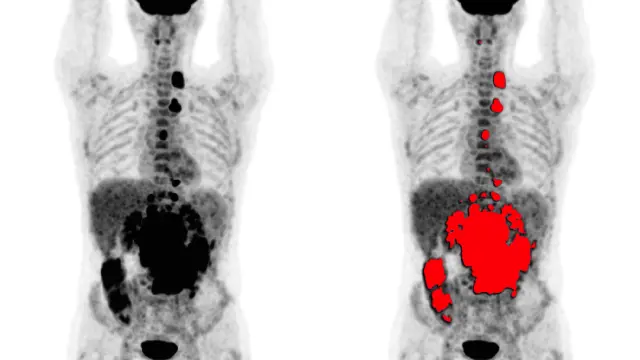

Los dispositivos PET se centran en la obtención de imágenes moleculares, que utilizan radiofármacos específicos para generar la imagen funcional de un órgano o proceso metabólico en particular. La imagen molecular mediante PET está ayudando en todas las etapas del estudio oncológico del paciente, tanto en el diagnóstico inicial como en el seguimiento, guía para biopsia o planificación de quimio/radioterapia.